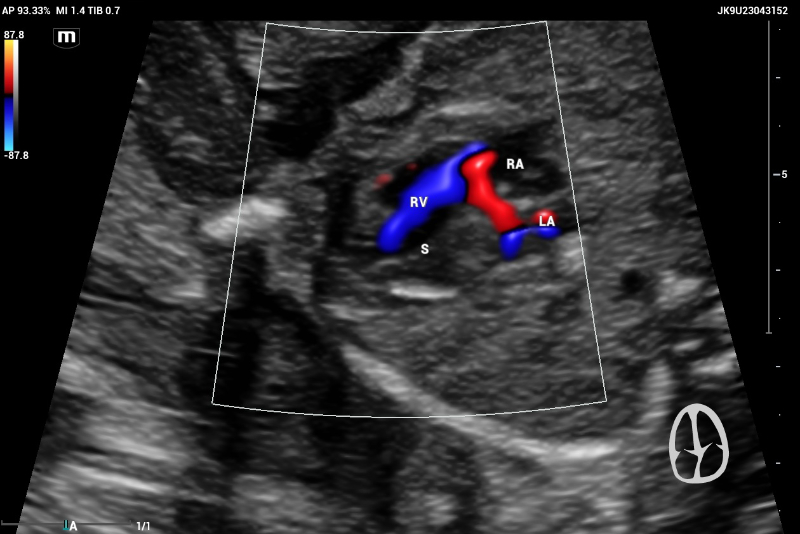

According to the ISUOG 2023 guidelines, second-trimester screening includes a standardized protocol for anatomical evaluation, incorporating fetal echocardiography. In a normal fetal echocardiogram, the ventricles should be symmetric and of equivalent size; any asymmetry is suggestive of disease (figure 1, and 2).

Example of Axial or transverse thorax image in fetal echocardiography showing a normal heart with symmetric 4-chamber view

Figure 1. Example of Axial or transverse thorax image in fetal echocardiography showing a normal hearth with symmetric 4 chambers view.

An example of normal echocardiography ultrasound screening showing Right ventricle (RV) and Left ventricle with normal filling

Figure 2. An example of normal echocardiography ultrasound screening showing Right ventricle (RV) and Left ventricle with normal filling.